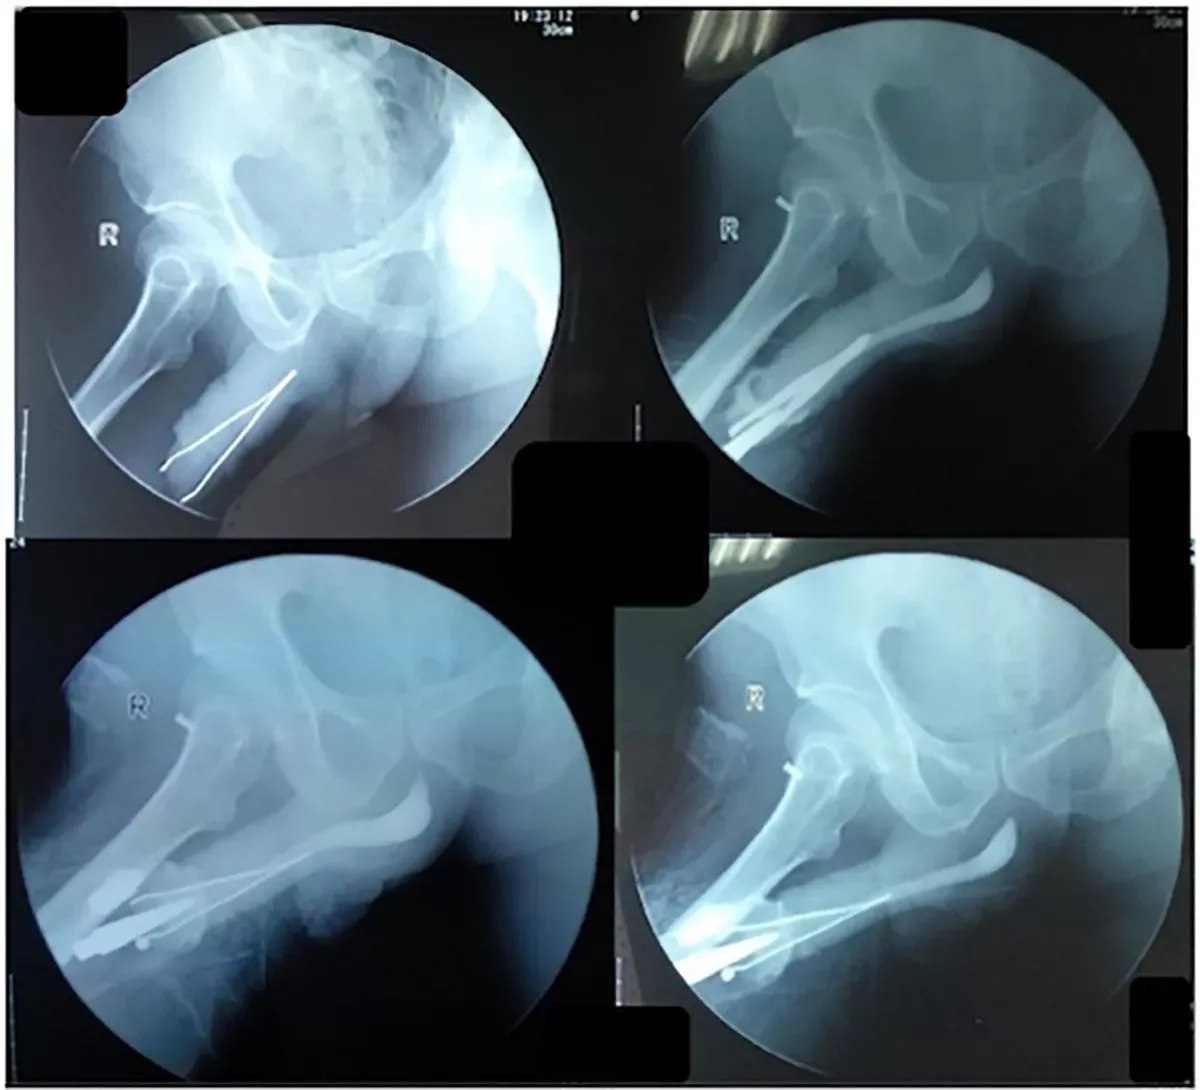

他照X光後,醫生驚訝地發現男子的陰莖裡竟塞了一把鉗子,且整把鉗子幾乎卡在體內。

印尼54歲男子的X光照,可見鉗子被卡在重要部位內。